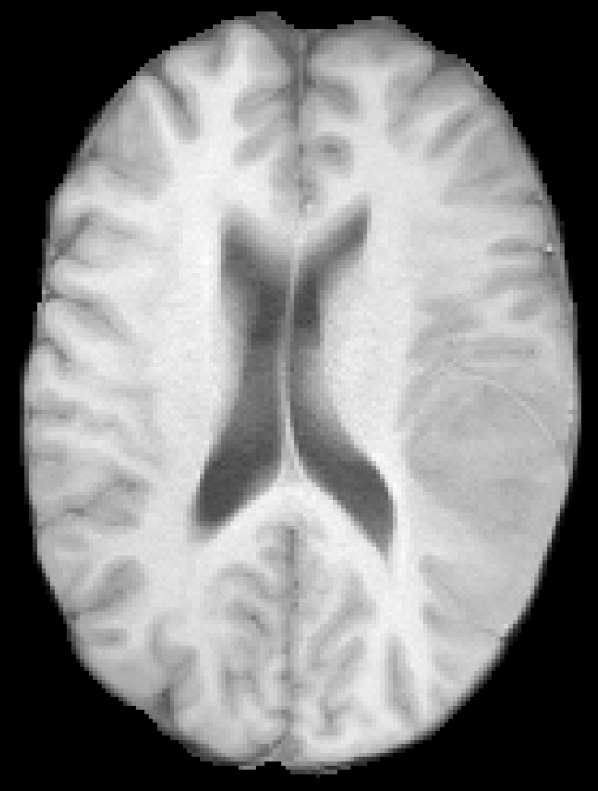

The given images are first pre-processed with a symmetric modality augmentation to allow learning of features based on the symmetry of brain hemispheres despite the small receptive field of the used patches. Explicit symmetry information was already shown to improve results for chronic stroke lesion segmentation [19]. In our case, instead of using one patch per hemisphere in a multi-path network we use a single joint patch with a single-path network. In practice, we augment the provided modality images with symmetric versions that swap the left and right hemispheres. We first flip one of the images along the mid-sagittal axis and then we apply FSL FLIRT [20] to perform a linear registration between the original and flipped image. Finally, the rest of modalities are registered using the same transformation. Figure 1 shows an example of the resulting symmetrically augmented modalities. These are then appended to the provided ones, effectively doubling the number of images for each patient. In this way, a single extracted patch will also include intensity information from the opposite hemisphere.

Refer to caption

(a) T1

(b) T2

(c) DWI

(d) FLAIR

Figure 1: Provided and symmetrically augmented modalities from case 2 of the SISS training images.